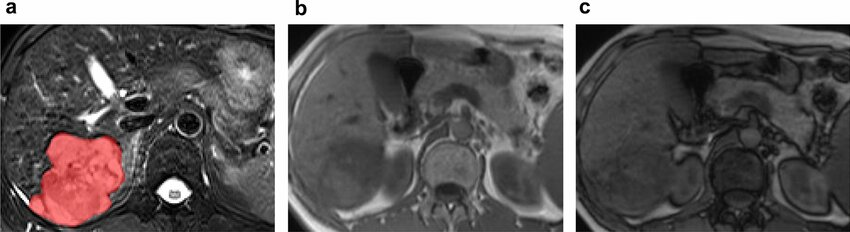

富粗梁型肝癌亚型 Macrotrabecular massive subtype -MTM –(5%)

组织病理特征 Histopathologic Characteristics

- 大于50%的肿瘤有大梁结构 Macrotrabecular architecture in >50% of tumor

临床考虑 Clinical Considerations

- 乙型肝炎 Hepatitis B

- a-胎蛋白水平高 High a-fetoprotein level

成像 Imaging

- 通常为LR5,坏死>20% Usually LR5 with necrosis>20%

- 混合性动脉低/高密度血管 Mixed arterially hypo/hyper-vasc

- 瘤内动脉Intratumoral artery

- 肿瘤边缘不光滑 nonsmocth tumor margin

- 冠状增强 corona enhancement

预后 Prognosis

- 差,早期血管侵润,早期转移,早期复发

|  |  |

|  |

| Macrotrabecular-massive subtype of hepatocellular carcinoma in a 62y man. The lesion shows heterogeneous high signal intensity on T2WI and was first segmented in red (a). The component of intralesion fat exhibit high signal intensity on axial in-phase T1-weighted image (b). And the signal drop on the out-of-phase image (c). The rad-score of this lesion was -13.862 |